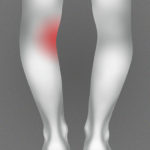

Polven nivelrikko Nivelrikko on aikuisten tavallisin polvikipujen syy. Nivelrikkoa voi olla reisiluun ja sääriluun välisessä nivelessä, mutta myös polvilumpion ja reisiluun välisessä nivelessä. Kirjoituksessa keskitytään yleisempään reisiluun ja sääriluun väliseen nivelrikkoon ja siitä on rajattu pois nivelrustovaurioiden hoito. Nivelrikko alkaa toisinaan vähitellen esimerkiksi lähestyttäessä keski-ikää. Yli 75- vuotiaista naisista vaivasta kärsii yli 30 prosenttia ja[…]